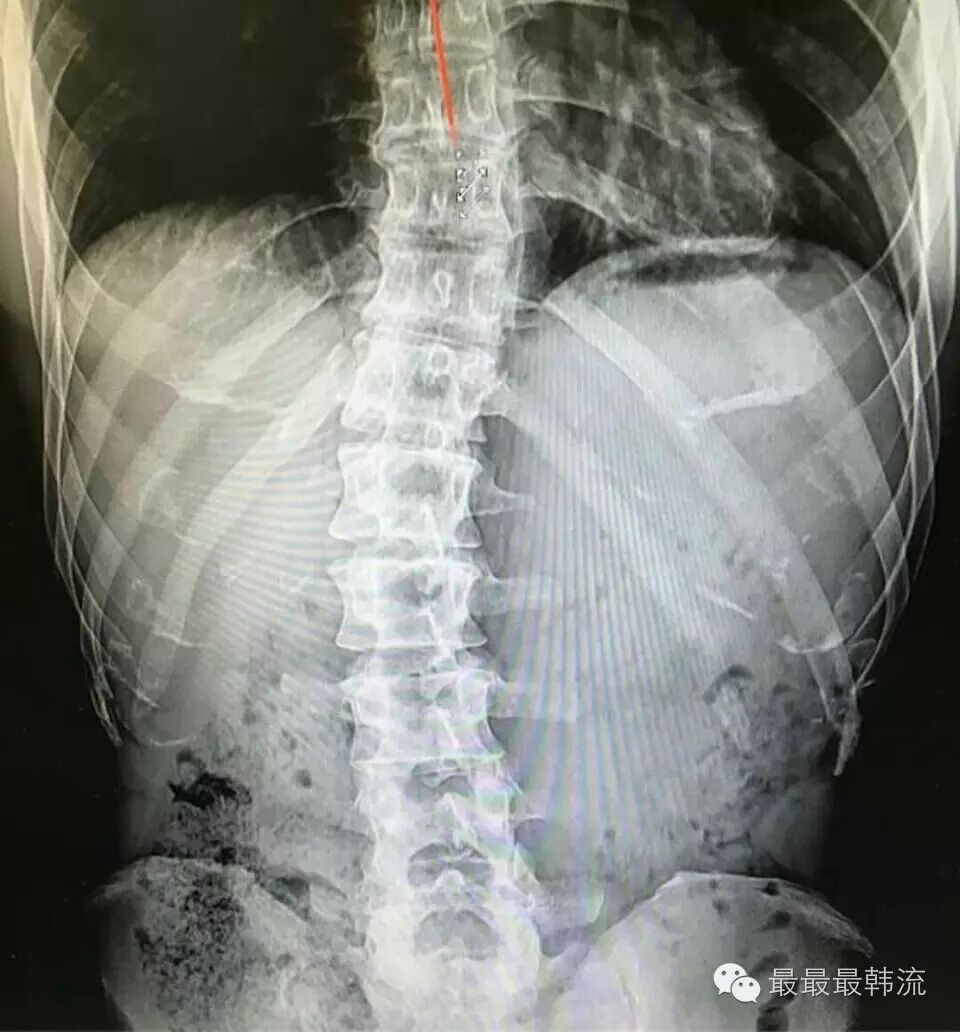

为了证明自己并没有伪造病历逃避兵役,金钟国晒出了自己背部的X光照片,并表示其实自己的脊柱处于非常不稳定的状态↓

看图的话的确看得出来,金钟国的脊柱弯了一段↓